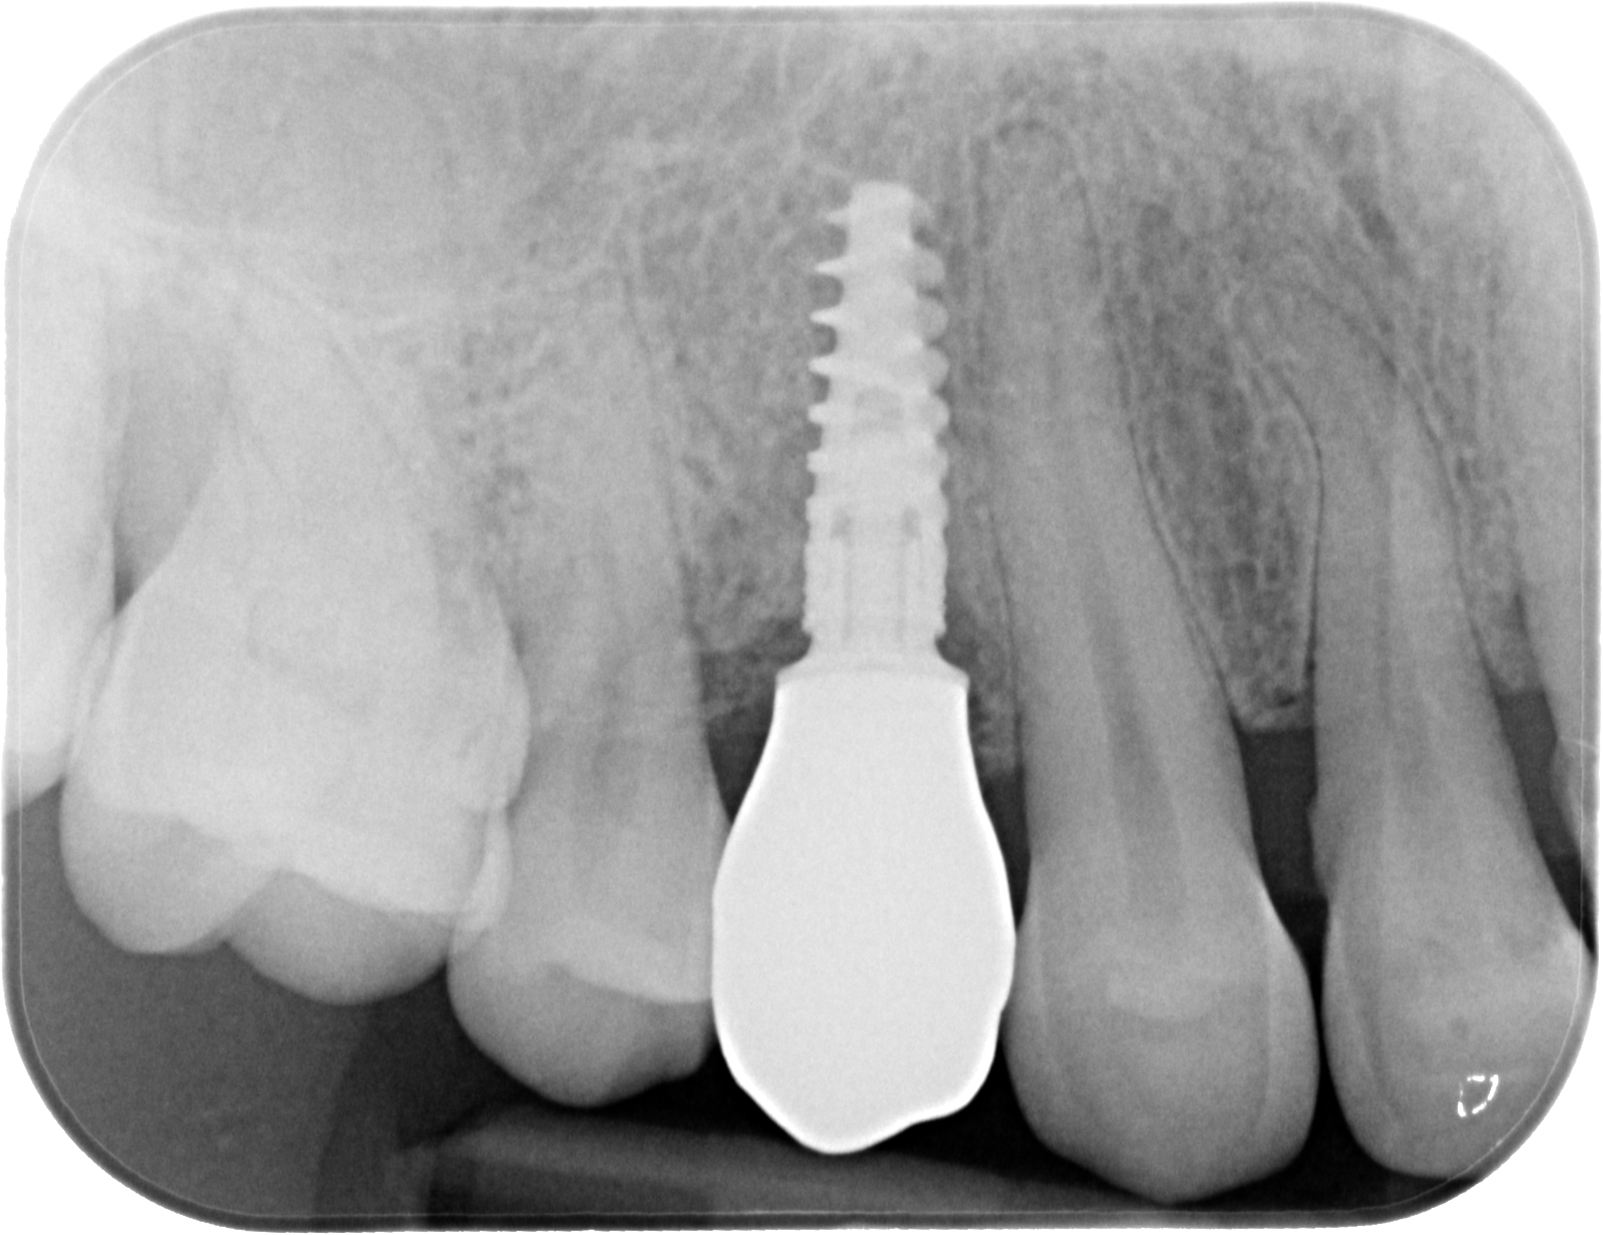

Fig. 02 : radiographie rétro-alvéolaire.

Fig. 03 : CBCT et planification implantaire (Nobel Active 3,5×13).

Fig. 06 : situation clinique à 4 mois de cicatrisation vue vestibulaire et vue latérale.

Fig. 07 : radiographie rétro-alvéolaire de contrôle après 4 mois de cicatrisation.